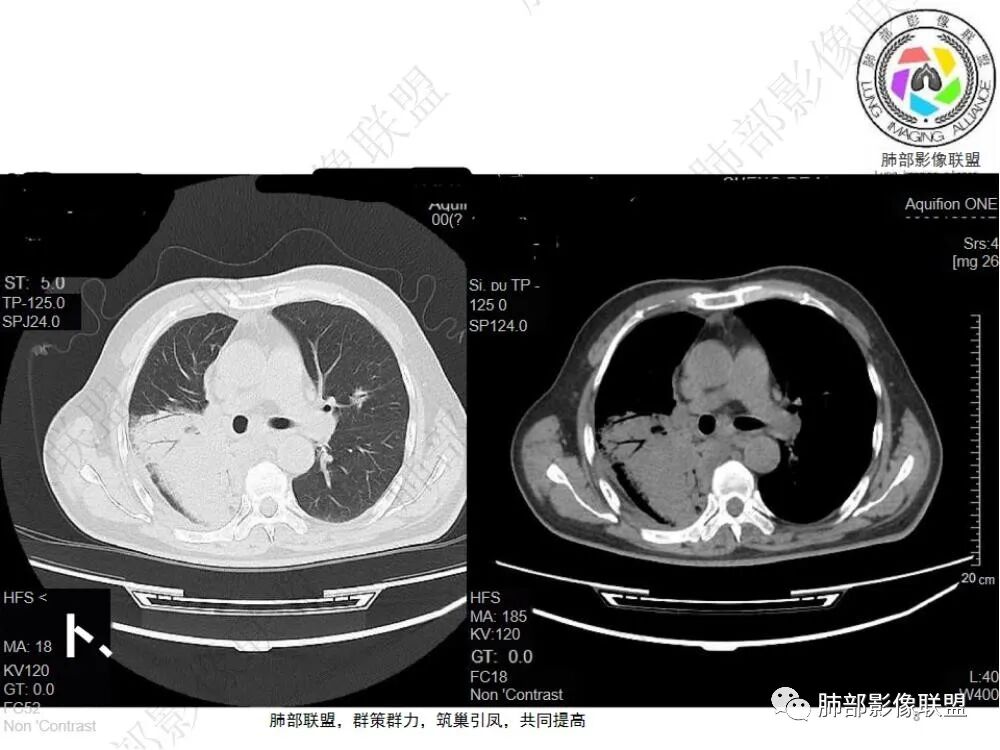

2.影像显示右肺上叶后段及右肺下叶较大范围实性密度为主片状影,边界可分辨,密度较均匀,隐约见小范围低密度(可疑液化区),未见钙化及气囊影。

3.左肺上叶见小片影,边界不清,实性及磨玻璃混合密度。

4.右侧胸腔积液,多包裹局限。

5.纵隔见轻度增大淋巴结。

6.一周后复查变化较为明显。肺部实变影有所吸收,但胸腔积液增加明显,包裹于侧胸壁、纵隔旁及叶间裂。注意右肺下叶因积液推压明显(可惜未能提供薄层图片及矢状位图片)。